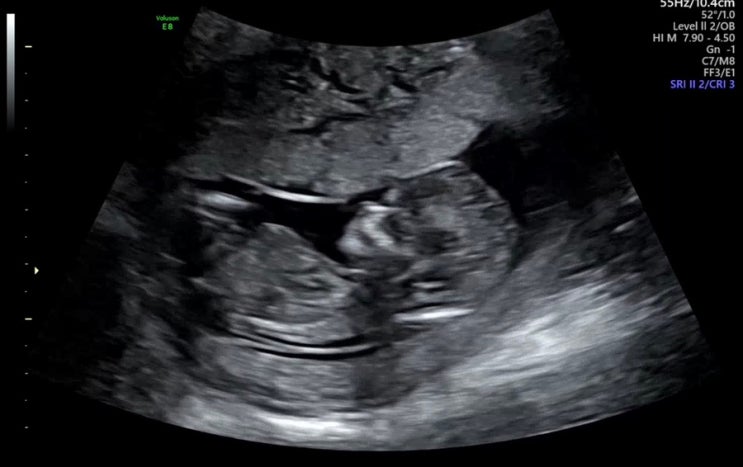

임신 12주 ~ 13주) 태아보험, 성별 추측, 군산 여행, 아기방 만들기

포스팅하면서 기록을 깜박했는데 태리는 11주에 태아보험 삼성화재 다이렉트 무려 1만 원대로,, 들었다 실...